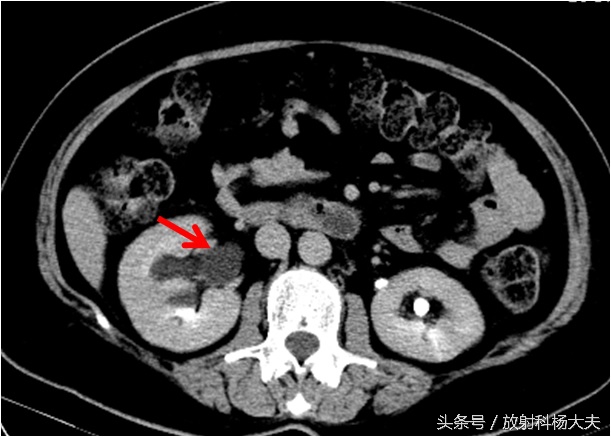

如下图就是宫颈的巨大肿瘤(圆圈所示),侵犯了右侧输尿管(红箭)。

引起了右肾积水。